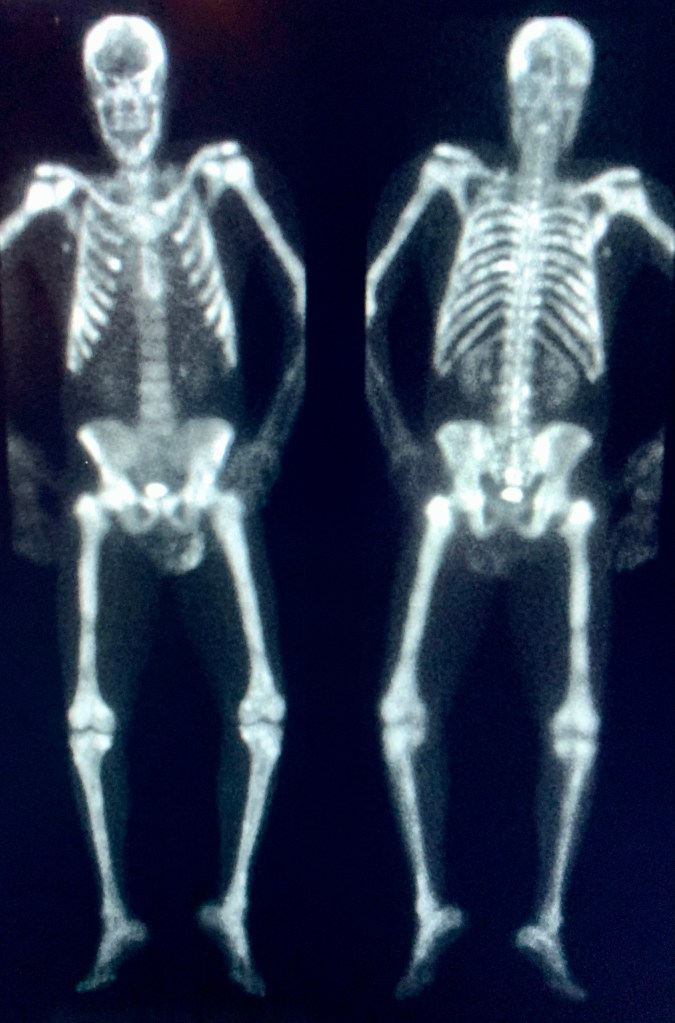

Dead Can Dance is an Australian duo that formed in 1981. Their music was described as “ethereal goth” in the early days but gradually evolved/expanded to include numerous worldly (and otherworldly?) influences, including African polyrhythms, Gaelic folk, Middle eastern, Gregorian chant, etc. I have an old friend who likes them, and that may be as close as I get. But I’m hoping to carve out the time for a deep dive. I think it’s good to keep some things in front of you. Most of all, death.

The band commented on their name and first self-titled album (per Wikipedia): “To understand why we chose the name, think of the transformation of inanimacy to animacy. Think of the processes concerning life from death and death into life. So many people missed the inherent symbolic intention of the work, and assumed that we must be ‘morbid gothic types’.”